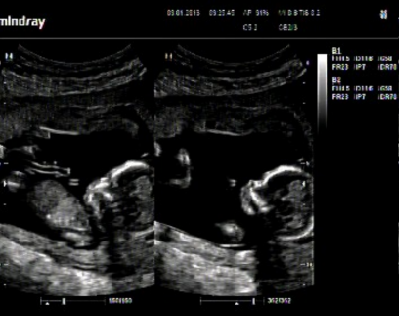

také přidávám foto z dnešního dne, je to jedna fotka složená ze dvou, nějak se nedařilo pořádně zabrat celého mimíska :-) , tak se můžete podívat na toho našeho drobečka